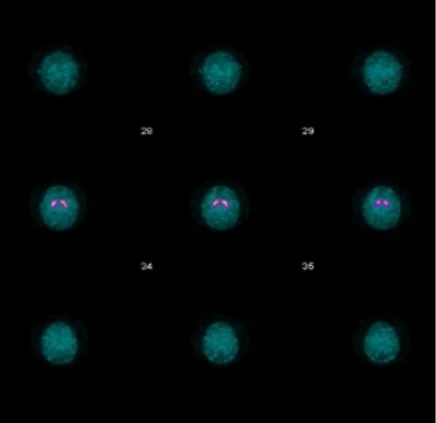

• Normal study = bilateral comma shaped shit in putamen region (pic to right)